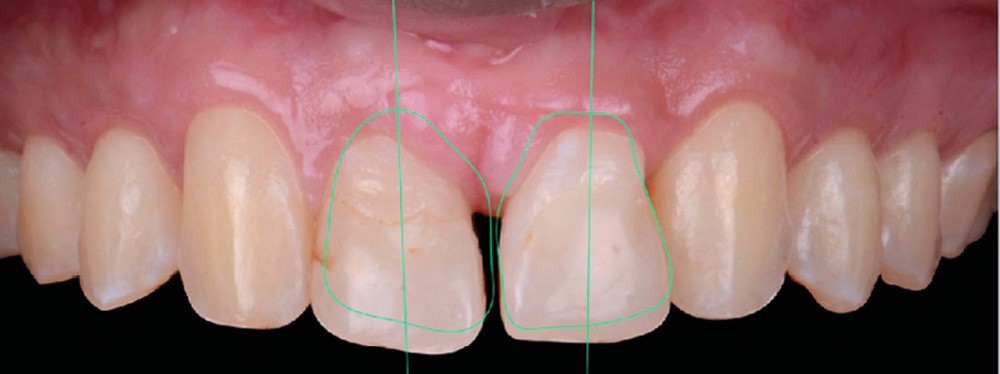

Une fois la croissance alvéolaire terminée, le patient est réadressé à son chirurgien-dentiste pour définir précisément, à l’aide d’une prévisualisation informatique (Digital Smile Design), quelle position dentaire et gingivale est recherchée pour les quatre dents antérieures (fig. 4 a,b) [4]. Le torque et le tip sont particulièrement importants à corriger dans cette phase de reprise de traitement (de quelques mois) car la position des collets et la conservation tissulaire en dépendent fortement.

Les restaurations composites transitoires réalisées au cours du premier traitement cherchant à restaurer l’esthétique de 12 et 22 masquent l’asymétrie de correction des axes radiculaires. La lecture des informations du deuxième et du troisième ordre est ainsi faussée par l’anatomie coronaire perturbée. Une individualisation par plicature est donc nécessaire pour s’approcher au mieux de la prévisualisation, avec pour seuls guides les axes radiculaires radiologiques et la position des collets souhaités (fig. 4a,b).

Plusieurs difficultés ont été rencontrées durant le traitement. L’impact psychologique des extractions d’incisives centrales a été lourd pour le patient, dont la promesse d’un sourire harmonisé a permis de surmonter cette épreuve. Ensuite, la gestion de la transposition était délicate. Il a fallu également accepter un rendu esthétique perfectible jusqu’à la fin de la croissance. La gestion de la dysharmonie dento-parodontale au niveau des incisives latérales et des canines était essentielle ; une correction parodontale et orthodontique, en jouant sur les informations de deuxième et troisième ordres, a permis une transition esthétique optimisée. L’outil de prévisualisation Digital Smile Design s’est en ce sens avéré très utile pour définir les impératifs propres à la prothèse (fig. 4a,b). Des frais pour la parodontie et la prothèse se sont enfin ajoutés aux dépenses orthodontiques (deux phases de traitement). Le rendu esthétique est satisfaisant en fin de traitement, avec une harmonisation du sourire et du profil (fig. 5 et 6). Les extractions n’ont pas appauvri le sourire. La qualité des réalisations prothétiques, l’environnement parodontal remanié et l’occlusion de fin de traitement font espérer un bon devenir dans le temps.